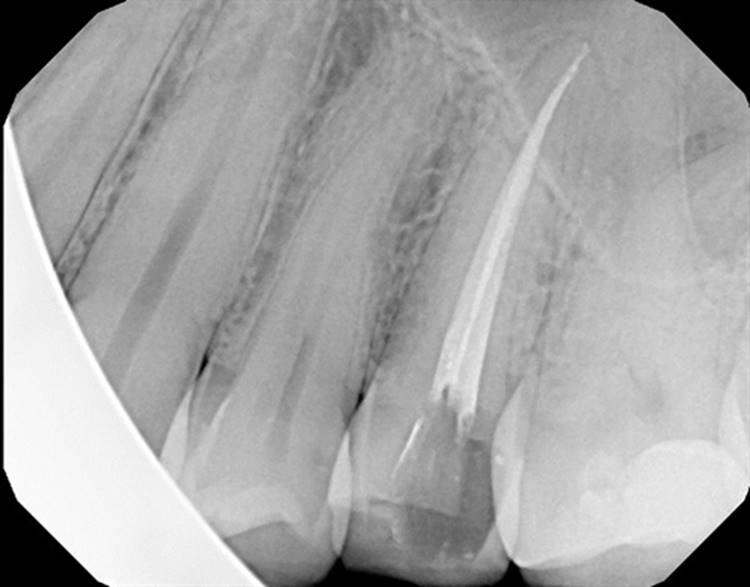

Forgive the sensor change from the first two cases to the last two. The good sensor broke and the back up isn’t as great.

EdgeFile® Cases